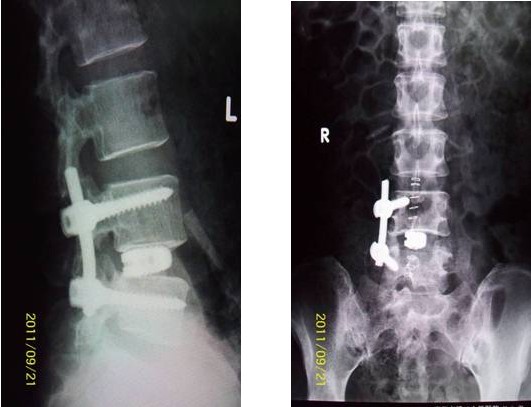

病例汇报1老年女性患者,因“反复腰腿痛10年、加重伴左下肢麻痛2月”之主诉入院,术前左下肢肌力3+级,浅感觉减退。术后腰腿疼缓解,肌力及感觉恢复正常。(1、图2)

术后腰椎X线提示单侧钉棒系统固定稳妥,椎间隙高度恢复正常,融合良好。(图2